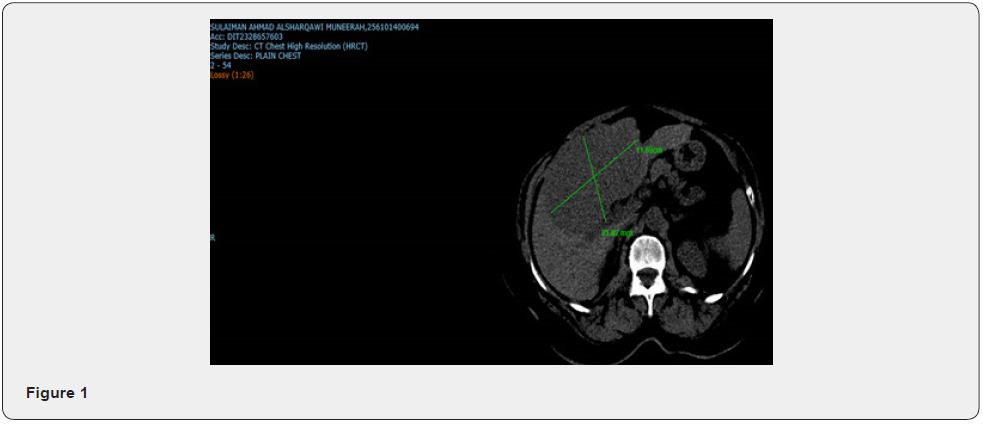

A 64-year-old woman presented with abdominal pain. Her past medical history was unremarkable. Her physical examination was also unremarkable. The heart and the lung were normal. There was hepatomegaly but no splenomegaly in abdominal examination. The head and neck examinations were also normal. There was no sign of icterus, cyanosis. Laboratory examination showed WBC = 9000/mL, Hb = 13 g/dL, and platelet = 250,000/mL. ALT, AST, GGT, and alkaline phosphates were all unremarkable. Tumour markers of CEA, CA125, CA19-9 and AFP were all in normal range. Colonoscopy was normal and CT scan showed an enlarged liver with a large mass in the right lobe of the liver with irregular borders and central necrosis, measuring 14 cm in the greatest diameter. A few smaller lesions were also present. Portal vein thrombosis was also identified. Non-tumoral liver was unremarkable, meaning that there was no underlying disease in the non-tumoral liver parenchyma (Figure 1). CT chest was normal with no bony metastasis.